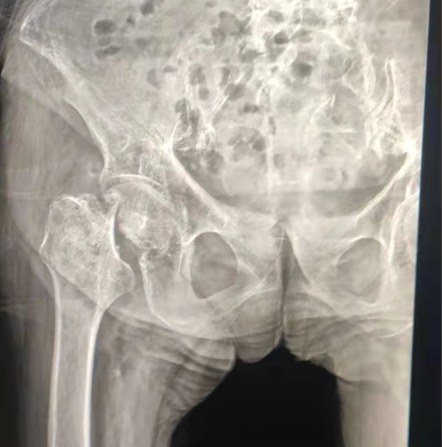

Case Sharing | Paciente de 70 anos, recebeu a substituição total do quadril com sistema de quadril cimentado Lepu

Sistema quadril cimentado:

Materiais liga Co-Cr-Mo

Alta resistência ao desgaste

Grande resistência mecânica